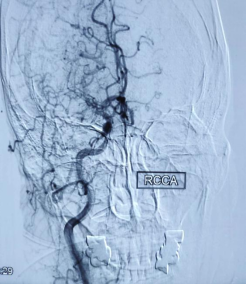

有一名老年女性患者,3月前出现头晕、言语不清,自觉舌头僵硬,就诊于我院内科门诊行颅脑磁共振平扫:新发脑梗死;颅脑血管磁共振:双侧大脑中动脉未见明确显示,颅内较多侧支血管形成,考虑烟雾病,建议脑血管造影检查。住院期间行脑血管造影:

看到这些图,瞬间让人想起了天青色等烟雨,而我在等你,炊烟袅袅升起......

烟雾病(Moyamoya disease,MMD),又称颅底异常血管网病,是颈内动脉虹吸部及大脑前动脉、大脑中动脉起始部严重狭窄或闭塞,软脑膜动脉、穿通动脉等小血管代偿增生形成脑底异常血管网为特征的一种脑血管疾病。其脑血管造影可见脑底密集成堆的小血管,酷似烟雾,故称为“烟雾病”。